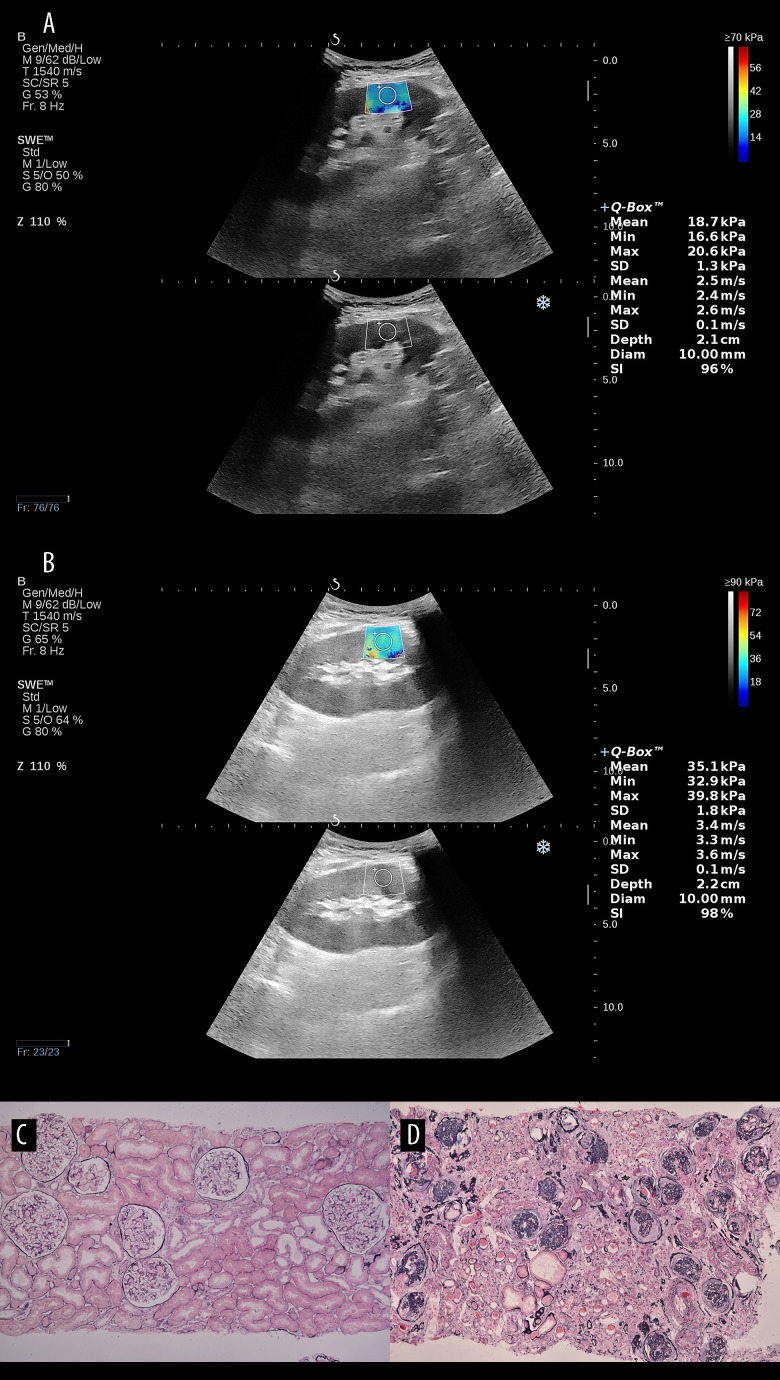

背景 本研究旨在探讨超声剪切波弹性成像(SWE)在评估肾移植术后患者肾脏纤维化方面的临床实用性。材料和方法 我们选择了 183 名接受肾移植的患者。完整的数据集被随机分为训练组(128 例)和验证组(55 例)。所有患者都接受了 SWE 和肾移植活检。基线数据采用 t 检验、Z 检验或卡方检验进行比较。通过单变量和多变量分析,我们确定了影响移植后肾纤维化的独立风险因素,建立了移植后肾纤维化的预测模型,并生成了校准曲线、决策曲线分析和 ROC 曲线。结果 年龄、TST、Scr、GFR 和 Emean 显示出显著差异(P0.05)。DCA 显示,预测模型有效提高了纤维化诊断的准确性。移植患者肾脏纤维化综合预测提名图的最高 AUC 值在训练组为 0.902,在验证组为 0.871。这些数值明显高于单个预测因子的 AUC 值(P

BACKGROUND The aim of this study was to investigate the clinical utility of ultrasound shear wave elastography (SWE) for assessment of renal fibrosis in post-renal transplant patients. MATERIAL AND METHODS We selected 183 patients who underwent renal transplantation. The complete dataset was randomly partitioned into a training cohort (128 cases) and a validation cohort (55 cases). All patients were subjected to SWE and renal allograft biopsy. The baseline data was compared using t-test, Z-test, or chi-square test. Through univariate and multivariate analyses, we identified independent risk factors influencing renal fibrosis after transplantation, a predictive model for post-transplant renal fibrosis was developed, and calibration curves, decision curve analyses, and ROC curves were generated. RESULTS Age, TST, Scr, GFR, and Emean showed significant differences (P<0.05). The C-index of the nomogram was 0.85, and the calibration curve and Hosmer-Lemeshow test demonstrated accurate diagnosis of fibrosis in both the training and validation sets (P>0.05). DCA showed that the prediction model effectively improved the diagnostic accuracy of fibrosis. The highest AUC of the nomogram for combined prediction of renal fibrosis in transplant patients was 0.902 in the training group and 0.871 in the validation group. These values were significantly higher compared to the AUCs of individual predictors (P<0.05). CONCLUSIONS Ultrasound SWE allows for early evaluation of renal fibrosis following transplantation. The prediction model, constructed by amalgamating other indicators, augments the accuracy and reliability of the prediction, providing more precise and accurate diagnostic and therapeutic recommendations for clinical practitioners.